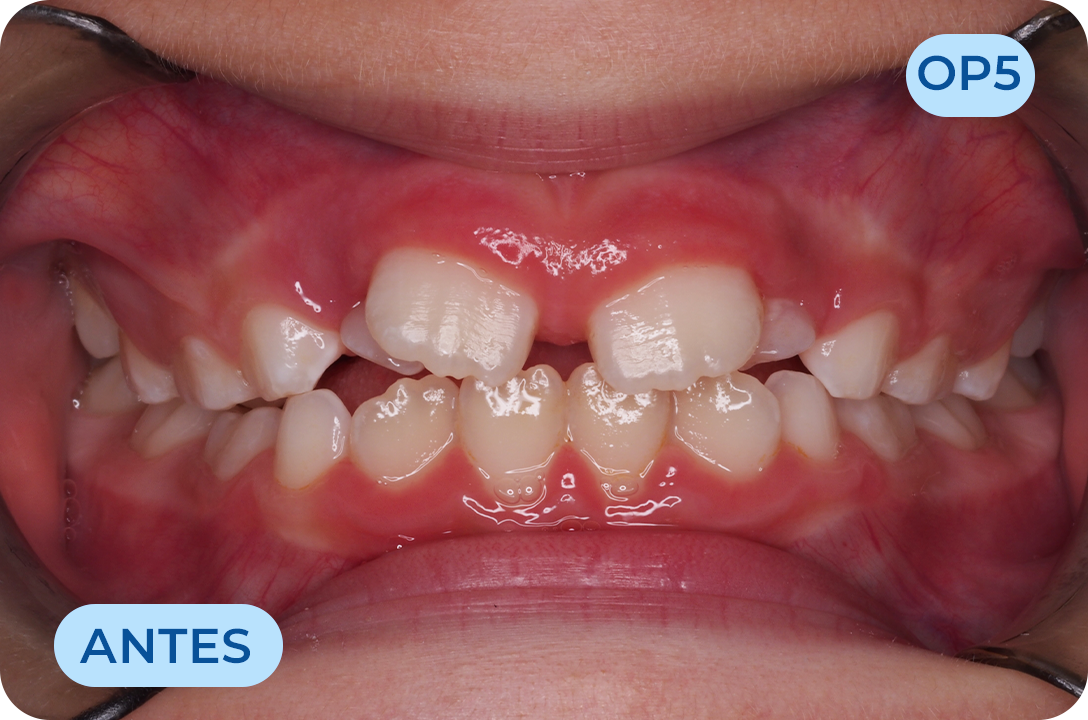

Odontologia Miofuncional

É a filosofia de tratamento que atua na reeducação da musculatura facial e mastigatória, corrigindo os maus hábitos miofuncionais como a respiração oral, deglutição atípica e posicionamento incorreto da língua, que não sendo resolvidos resultam em deformidades esqueléticas, dentárias e funcionais graves para a saúde geral do indivíduo. O sistema myobrace desempenha um papel importante nesta área.